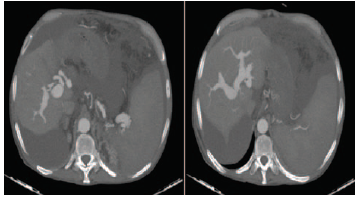

During the hospital stay, the patient had a sudden clinical decline with a progressive increase in ascites and a dramatic rise in serum bilirubin (up to 21 mg/dL) without significantly increased transaminase levels. In view of unexplained deterioration, a triphasic computed tomography (CT) scan was done. The CT scan showed rapid contrast flow in both the portal and hepatic arterial phase with a communicating fistula between the hepatic artery and portal venous system (Figure 2).

Figure 2. Axial Sections of Computed Tomography Scan Showing Simultaneous Rapid Flow of Contrast in Hepatic Artery and Portal Veins